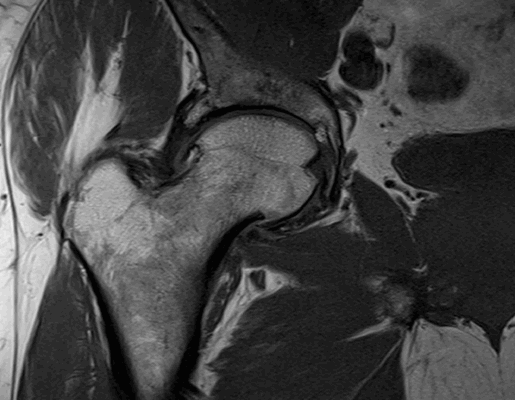

Импиджмент синдром на МР-фото

К механическому конфликту между бедренной головкой/шейкой и краем вертлужной впадины приводят одно- или двусторонние дефекты костей врожденного или приобретенного генеза. Видоизмененные компоненты сочленения вызывают дисфункцию конечности за счет соударения во время движения. Патологическое трение костей способствует разрастанию остеофитов на фоне постоянной травматизации вертлужной губы. Если своевременно не диагностировать заболевание и не начать лечение, последняя с течением времени разорвется., Хрящевая ткань сочленяющих костей будет разрушена. Подобный механический конфликт часто способствует формированию коксартроза и сопровождается прогрессирующим болевым синдромом.

МРТ тазобедренного сустава при феморо-ацетабулярном импинджмет-синдроме показывает возможные причины заболевания:

врожденные пороки развития;

осложнения после травм и оперативных вмешательств;

сопутствующий аваскулярный некроз головки бедра;

воспалительные процессы в синовиальной сумке;

остеохондропатию (болезнь Пертерса);

эпифизеолиз (перелом Салтера-Харриса);

атрофированные мышцы вокруг сочленения и пр.